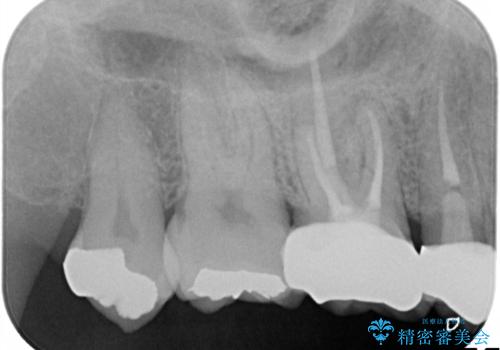

奥歯が痛い。精密根管治療〜オールセラミッククラウン

奥歯の根管治療~オールセラミッククラウン